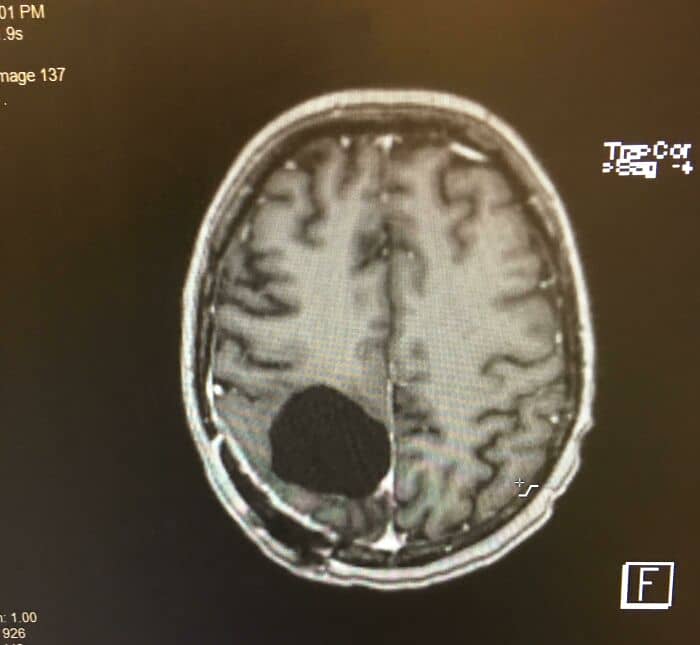

#33 Went In For Teeth Cleaning Last Month & Mentioned A Numb Feeling In A Tooth- I Was Shocked To Find A Tumor Eating My Jaw Bone. This Photo Is My Ct Scan. Biopsy Surgery Results Were Non-Cancerous, Thankfully

I had surgery last week to take a biopsy to rule out bone cancer. Results came back as a central large cell granuloma. Next step are more tests and a surgery to remove the tumor/lesion completely. Possibly bone transplant/stem cell procedure later to help regrow some bone and pretty sure those teeth will need help later down the line too. 15-20% chance this thing could come back, too.

#41 I Had A Brain Tumor Removed, And Now I’m A Bit Absent Minded